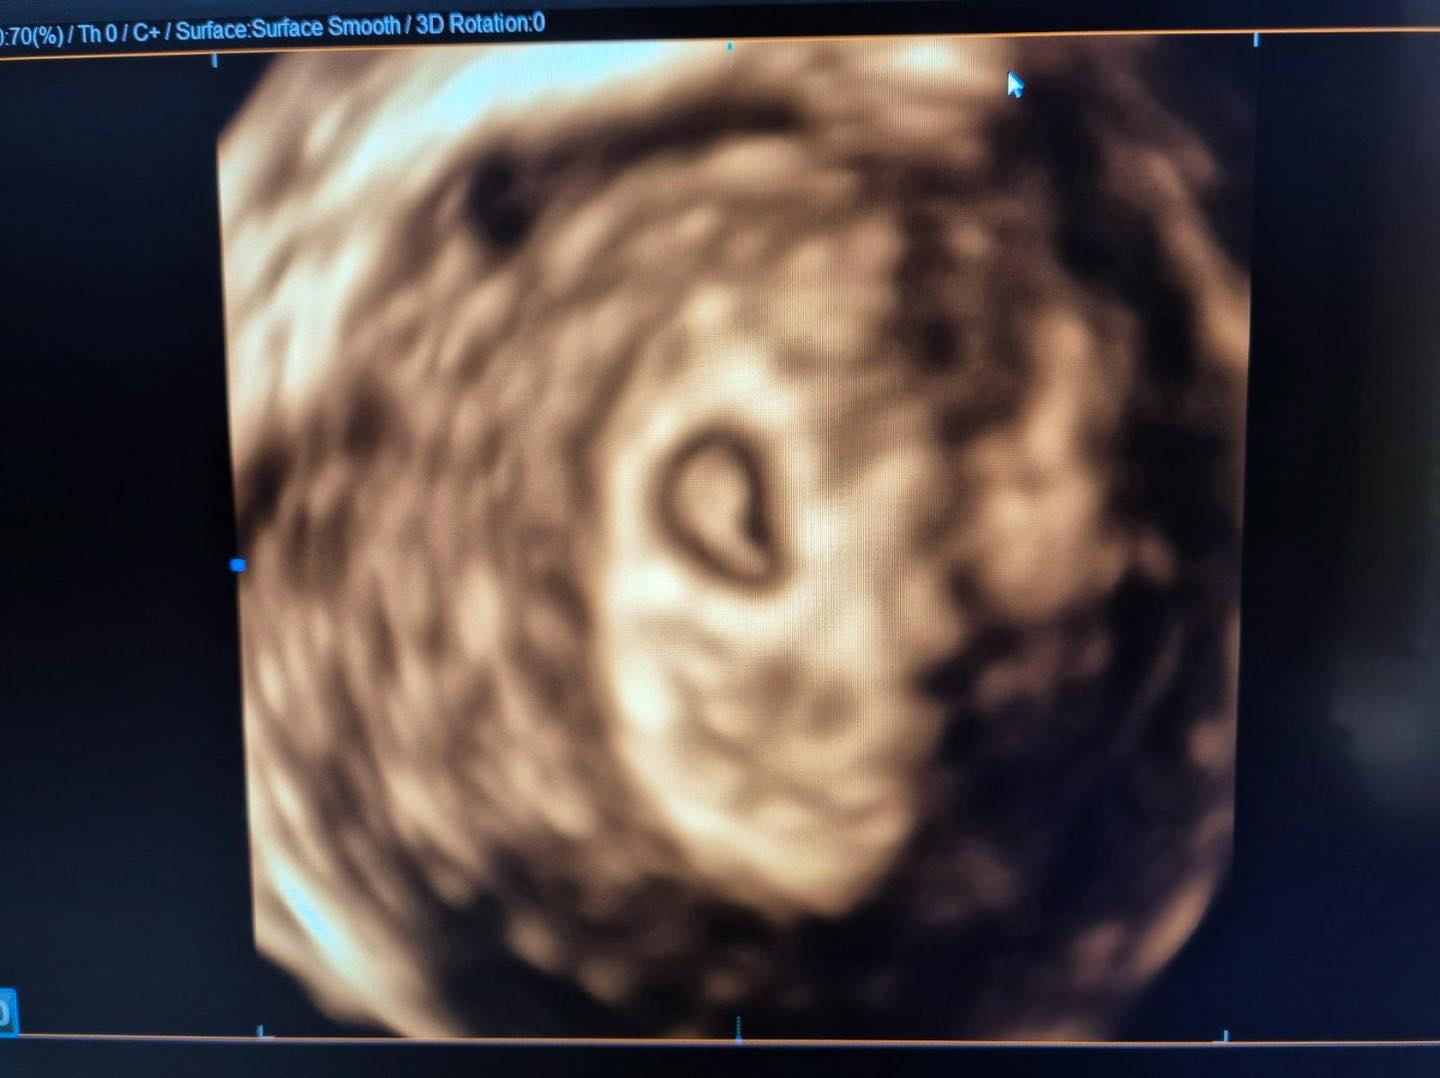

По успешно изведена лапароскопска миомектомија и хистероскопија, како и ин витро постапка со донирани јајцеклетки, таа го доби најдрагоценото –бременост!